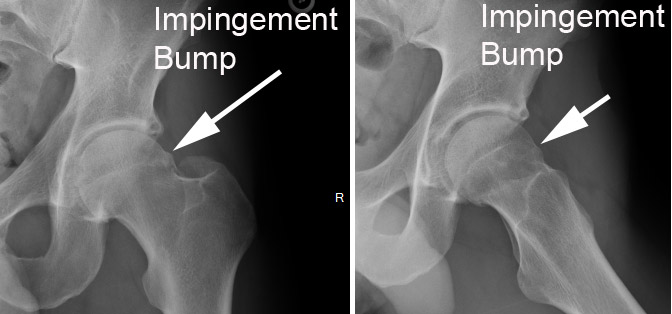

There are two types of hip impingement, “cam” type and “pincer” type. As a simplification, cam type is when the femoral head is too large for the socket and pincer type is when the socket is too deep. When either or both of these situations exist, the hip can become damaged with routine activities, leading to pain and loss of function.